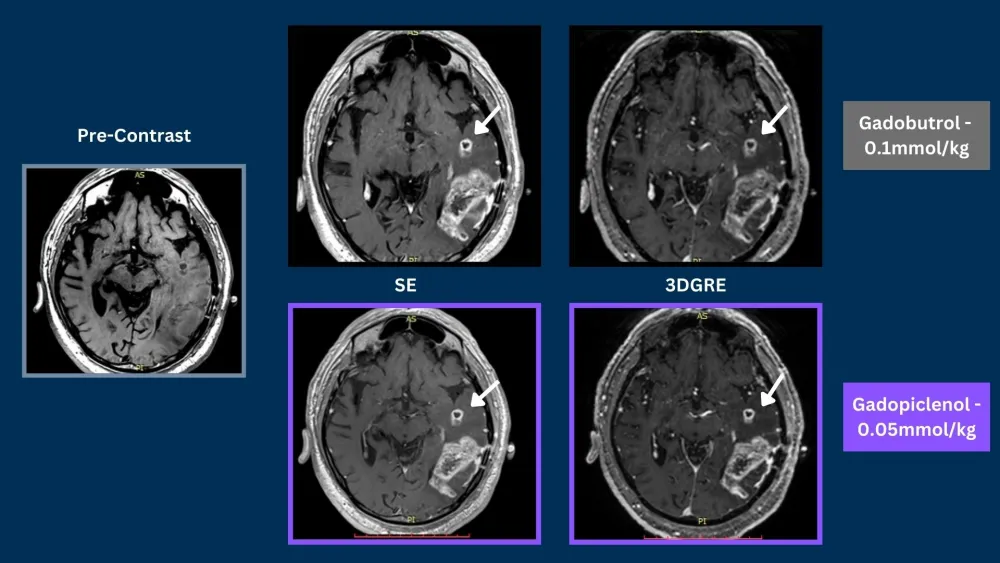

Phase III clinical trials, in CNS and Body, demonstrated that gadopiclenol at a dose of 0.05 mmol/kg was noninferior to gadobutrol at a dose of 0.1 mmol/kg in terms of lesion visualization.5,6

Case 579 year old male1

Glioblastoma

SE = Spin Echo, GRE = Gradient Echo, 3DGRE = 3D Gradient Echo, TSE = Turbo Spin Echo

Phase III PICTURE trial in CNS demonstrated that gadopiclenol at a dose of 0.05 mmol/kg was noninferior to gadobutrol at a dose of 0.1 mmol/kg in terms of lesion visualization.5